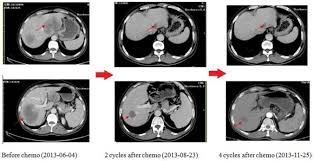

When you hear that cancer is in remission, is that the same as cured? For lymphomas, pr is defined as a ↓ by ≥ 50% of the longest perpendicular diameter of all measurable lesions. A partial response is most often defined as at least a 50% reduction in measurable tumor. Partial remission is achieved when a patient's tumors have shrunk by at least 50% in size and remain shrunken for at least one month. In complete remission, all signs and symptoms of cancer have disappeared, although cancer still may be in the body. If you remain in complete remission for 5 years or more, some doctors may say that you are cured. For a cancer that occurs throughout the body, such as leukemia, it can also mean that the amount of cancer cells has lowered. Cf complete remission , minimal response. If a patient had a plasmacytoma (a single lesion), a partial response would mean over a 50% reduction in tumor size. Usually, partial remission is determined if a tumor size has decreased by 50 percent and has remained that size for at least one month. Partial remission partial remission indicates that cancer has shrunk or stabilized for a period of time. Partial remission means the same things as a partial response. For mesothelioma, partial remission often alleviates many signs and symptoms, though the patient will still show some evidence of disease because the tumors are not completely gone.